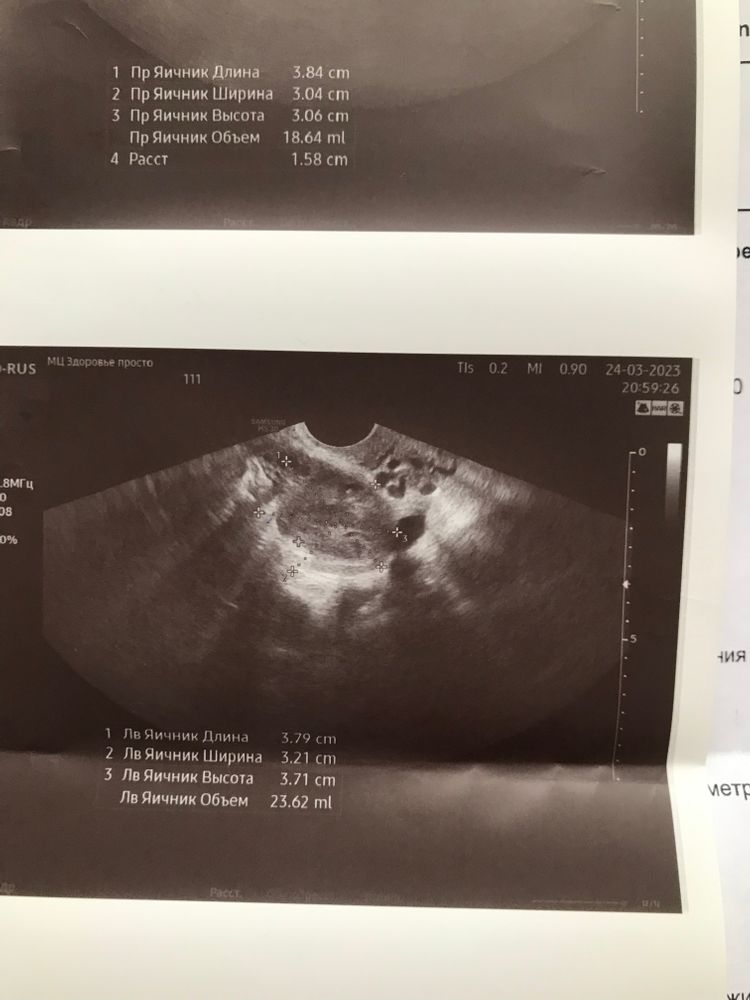

Замершая беременностьв правом 18 мм

в левом 23 мм

Дарья , то что вы пишете 18 и 23 это обьем яичника, а не желтые тела же, честно говоря, по этим фотографиям мне непонятно, где желтое, просто размеры.

Дарья , прочитайте внимательнее, это обьем) он складывается из трех измерений яичника, которые сделаны выше и автоматически рассчитывается аппаратом.